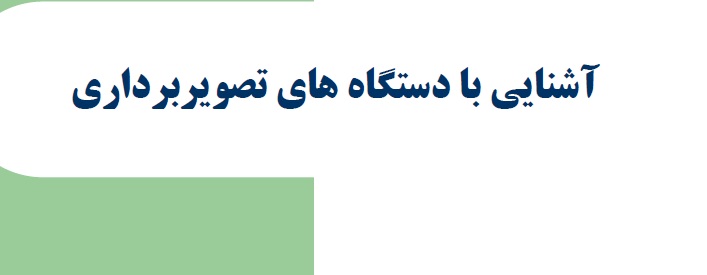

قیمت: 76٬000 تومان - دسته بندی فایل: علوم پزشکیآشنایی با دستگاههای تصویربرداری

فروش ویژه نسخه حرفه ای آشنایی با دستگاههای تصویربرداری با تخفیف استثنایی فقط 49 هزار تومان تعداد صفحات: 66 صفحه